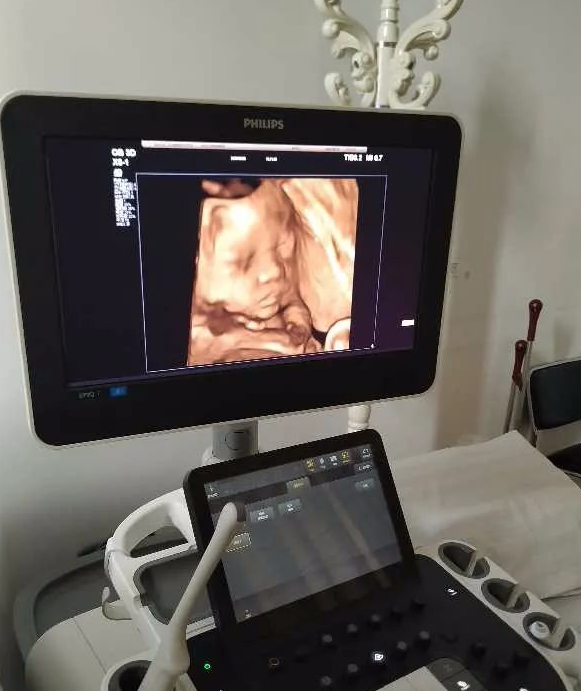

隨著彩超四維成像的發(fā)展,現(xiàn)在來國文醫(yī)院做四維彩超就可以看到腹中胎兒可愛的模樣了:淘氣的寶貝有時伸出舌頭,有時會啃著小手,有時會手擋著臉害羞,不讓我們看呢!